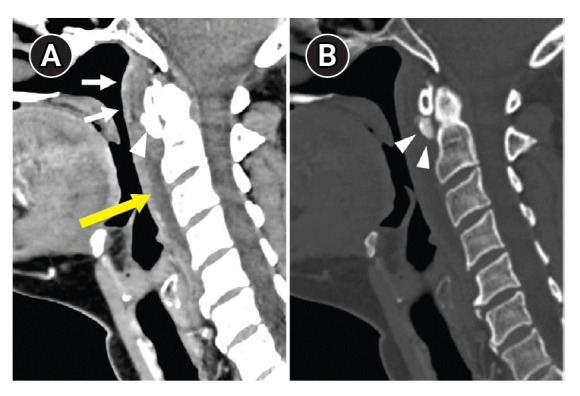

Calcific tendinitis of the longus colli muscle.

领长肌钙化性腱鞘炎